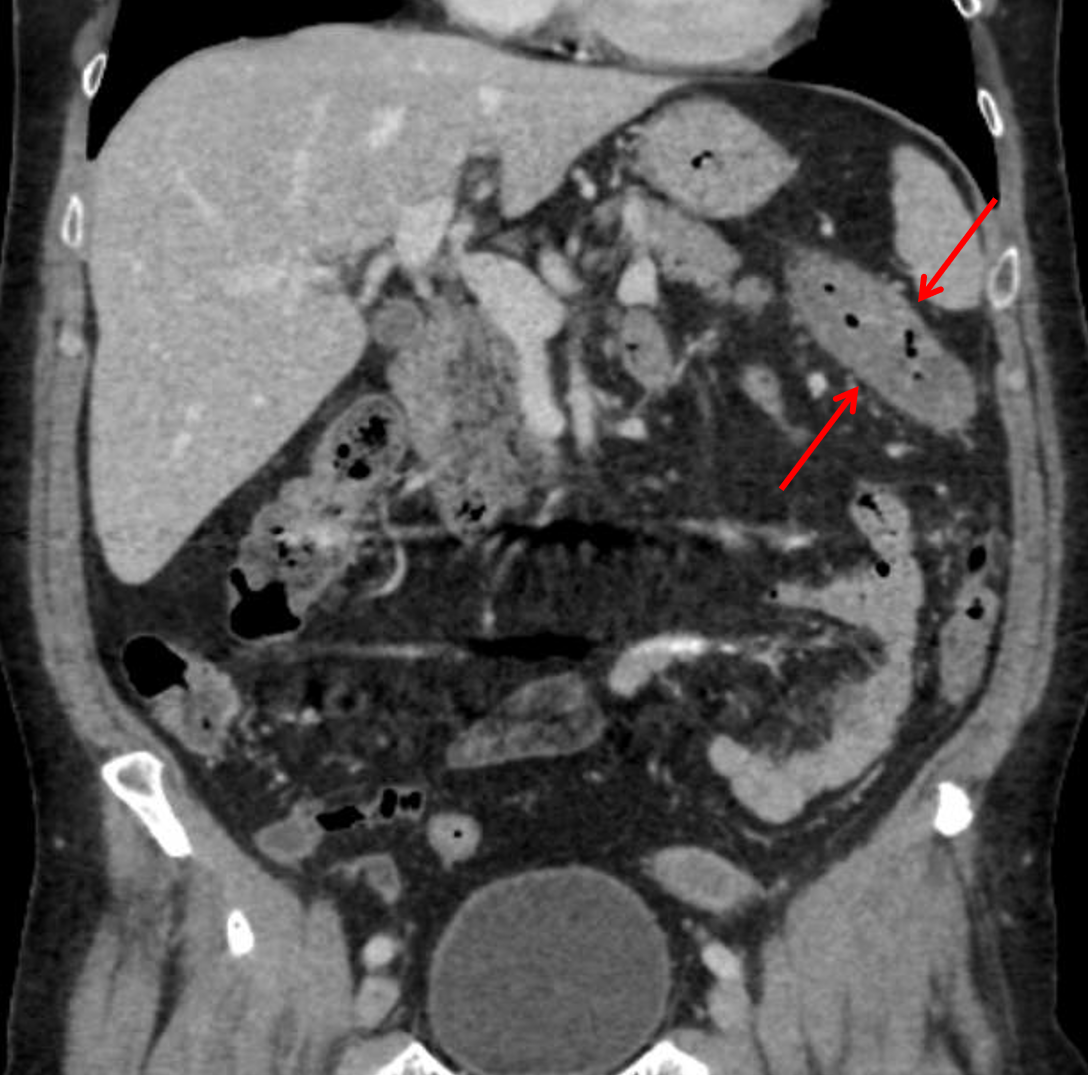

• Mural thickening of the splenic flexure of the colon extending into the proximal descending colon with mild pericolonic fat stranding

• Ischemic colitis

Short segment colonic mural thickening centered on the splenic flexure which given the clinical history and underlying vascular disease raises concern for ischemic colitis, although infectious/inflammatory colitis could have a similar appearance. No pneumatosis or portal venous gas.

Short segment mural thickening centered about the splenic flexure of the colon (red arrows), which in this clinical context is concerning for ischemic colitis.